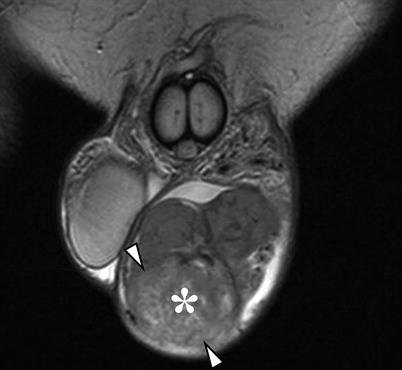

Кисты мужских половых органов – доброкачественные образования, локализующиеся в области мошонки, полового члена или придатка яичка. Наиболее часто встречаются кисты придатка яичка (сперматоцеле) и кисты семенного канатика. Хотя большинство кист протекают бессимптомно, в ряде случаев они могут вызывать дискомфорт, боли или косметический дефект, что требует хирургического вмешательства. Клиническая картина и диагностика Пациенты с кистами мужских половых органов могут предъявлять жалобы на: Диагностика включает: 1. Физикальный осмотр – пальпация образования, оценка его подвижности, плотности и связи с окружающими структурами. 2. Ультразвуковое исследование (УЗИ) мошонки – золотой стандарт диагностики, позволяющий дифференцировать кисту от опухолей, гидроцеле или варикоцеле. 3. Диафаноскопия (просвечивание мошонки) – кисты обычно пропускают свет, в отличие от плотных опухолей. Показания к хирургическому лечению Методики оперативного лечения 1. Иссечение кисты придатка яичка (сперматоцеле)

2. Ультразвуковое исследование (УЗИ) мошонки – золотой стандарт диагностики, позволяющий дифференцировать кисту от опухолей, гидроцеле или варикоцеле.